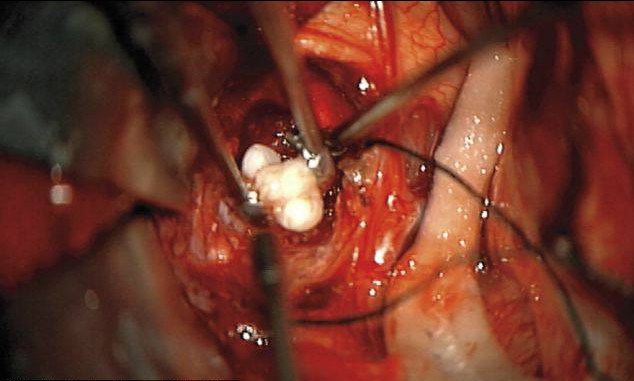

Doctorii au reusit sa ii scoata aceasta tumoare, iar copilul se simte bine.

“Nu vezi in fiecare zi un dinte care sa creasca intr-o tumora”, a spus doctorul Narlin Beaty, care a efectuat operatia.